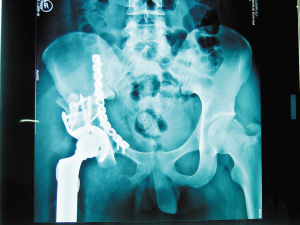

20世紀70年代以前,發生於骨盆區的惡性骨腫瘤大多數需要行半骨盆截肢術。隨著化療和放療等輔助治療方法的發展、先進影像手段的出現以及手術技術的提高,到21世紀初,一些原來只能靠截肢才能治療的腫瘤也可以施行保肢手術。

手術分型

肌肉骨骼系統腫瘤協會提出了骨盆腫瘤切除術的分型,按解剖學部位(髂骨為I區,髖臼區為II區,閉孔區為III區)將手術類型分為:

I型:髂骨切除;

II型:髖臼切除;

III型:閉孔區切除;

IV型:涉及骶骨的切除。

若同時切除兩個或以上區域,則切除類型為相應區域的組合,如同時切除髂骨和髖臼區,則手術類型為I、II型。切除整個骨盆為I、II、III型。若同時切除股骨頭,則為H型(如IIH;I、IIH,II、IIIH)。